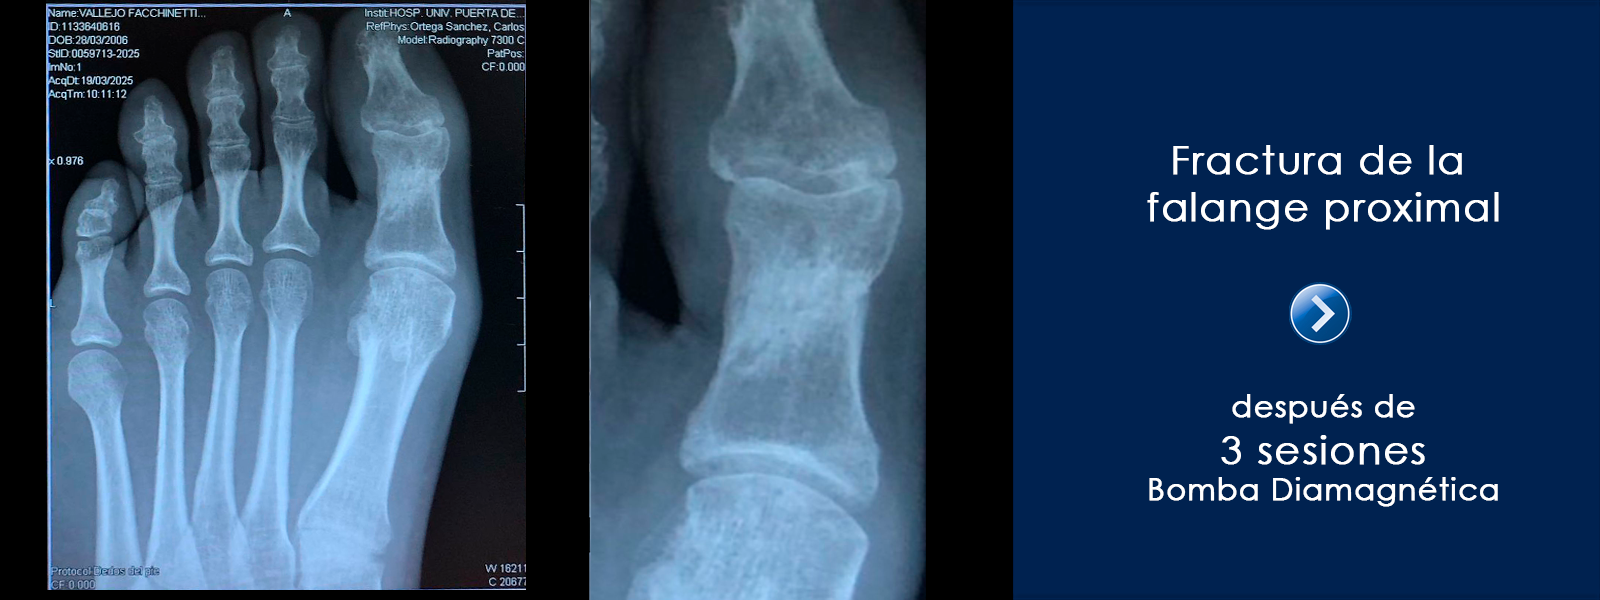

Después de la tercera sesión el paciente no manifiesta dolor y se aprecia claramente en la imagen la evolución en la consolidación de la fractura.

Conclusiones

Sin duda una evolución espectacular. El paciente venía con una fractura que no terminaba de consolidar, y despúes de 3 sesiones de Bomba Diamagnética, el cambio es notable. Además de la modulación del dolor.

Testimonio del Fisioterapeuta

Un caso más en el que la Bomba Diamagnética muestra su capacidad de regeneración ósea. Un gratificante caso en el que la imagen inicial mostraba claramente el retardo en la consolidación de la fractura y cómo después de sólo 3 sesiones, se puede apreciar un cambio tan notable en la evolución de la misma.